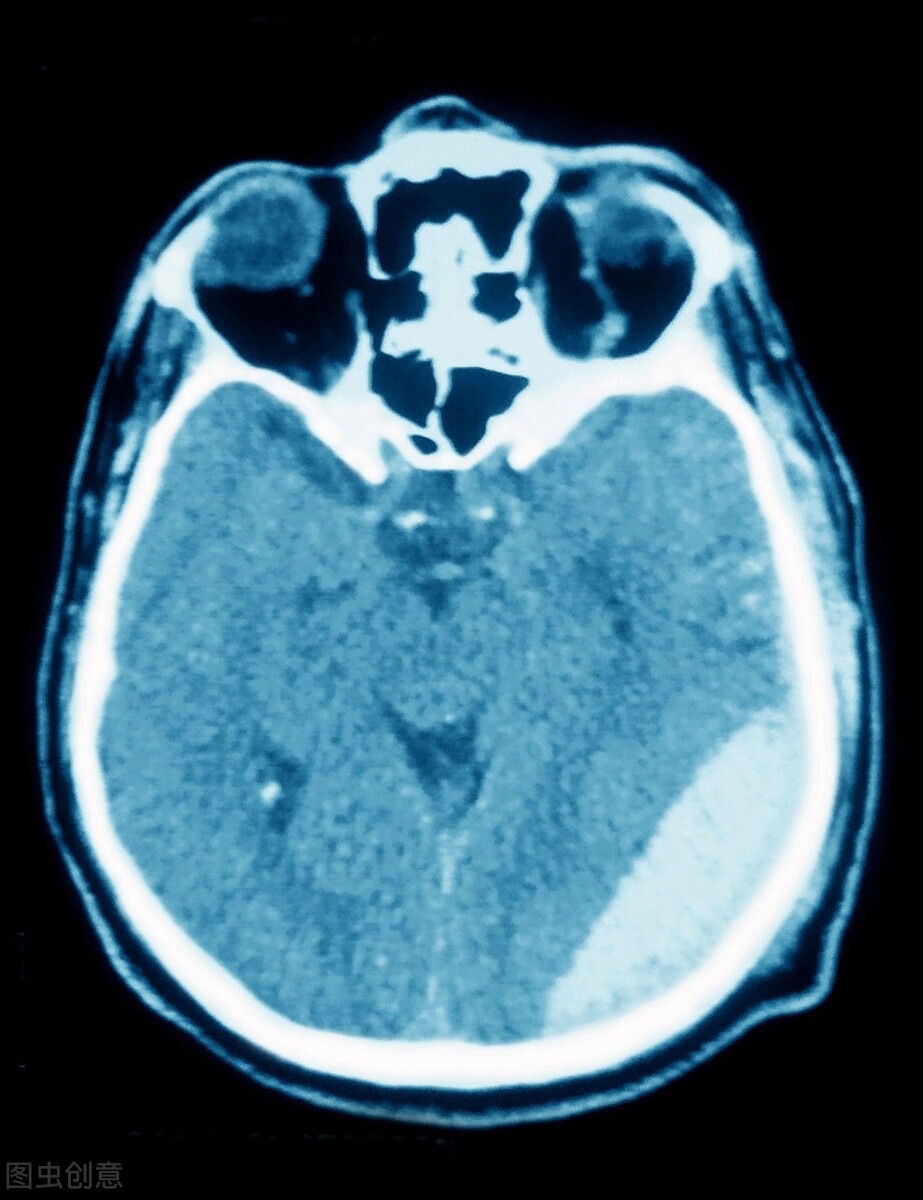

郑医生一边问着,一边又打开PACS系统,结果发现报告已经更改了:硬膜外血肿!

点开影像,仔细翻看,结果果然看到了左额颞部6mm宽的血肿。

很明显,这是对冲伤!

硬膜外血肿

所谓对冲伤,即头部受外力作用时,于着力处的对侧部位的脑部发生损伤,称为对冲伤。对冲伤多见于头颅撞击外界物体而致伤者,少见于受打击致伤者,即减速运动,如车祸多见。